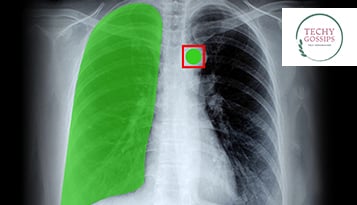

Why Data Annotators are the key to the Growth of Medical AI?

• Data annotation tools can be used in healthcare for scaling the healthcare process, improving the quality of AI resources, offering top-notch security and building better workplace experiences for healthcare professionals and customers as well.